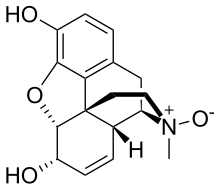

Several semi-synthetic opioids were developed in Germany in the 1910s. The first, oxymorphone, was synthesized from thebaine, an opioid alkaloid in opium poppies, in 1914.[228] Next, Martin Freund and Edmund Speyer developed oxycodone, also from thebaine, at the University of Frankfurt in 1916.[229] In 1920, hydrocodone was prepared by Carl Mannich and Helene Löwenheim, deriving it from codeine. In 1924, hydromorphone was synthesized by adding hydrogen to morphine. Etorphine was synthesized in 1960, from the oripavine in opium poppy straw. Buprenorphine was discovered in 1972.[228]